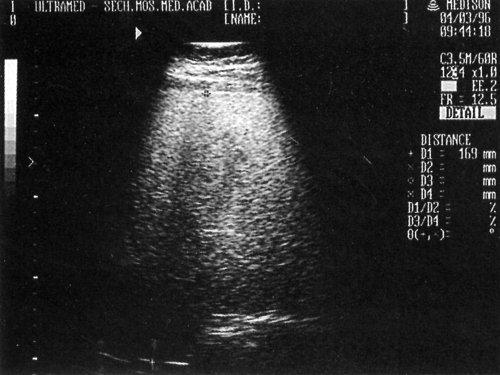

Ультразвуковое исследование печени можно проводить в любое время без предварительной подготовки. Обследование проводится, как правило, в трех плоскостях (продольной, поперечной и косой) со стороны правого подреберья и эпигастрия. При этом необходимо оценить расположение, форму, контуры, размеры, структуру и эхогенность паренхимы, сосудистый рисунок в целом и конкретные сосуды, протоковую систему, влияние окружающих органов на состояние изображения печени. Точность диагностики выявляемых изменений возрастает при динамическом наблюдении (схема 3).

В норме большая часть печени располагается справа от позвоночника, а меньшая - слева от него и доходит до левой парастернальной линии. Контуры печени ровные, она имеет четкое очертание, капсула хорошо просматривается в виде гиперэхогенной структуры, окружающей ее паренхиму (за исключением участков, прилежащих к диафрагме, где капсула не дифференцируется от последней). В норме нижний край печени не выступает из-под реберной дуги. Общепринятыми являются измерение косого вертикального размера правой доли (не превышает 13-15 см) и толщины левой доли (до 5 см). Структура неизмененной печени представлена мелкозернистым изображением, состоящим из множества мелких точечных и линейных структур, равномерно расположенных по всей площади полученного среза. По эхогенности паренхима нормальной печени сопоставима или несколько выше эхогенности коркового вещества почки (при отсутствии ее патологии). Эхография позволяет дифференцировать различные трубчатые структуры, находящиеся в печени.

Рис. 5. Эхографическая картина жировой инфильтрации печени - повышение эхогенности паренхимы с эффектом ослабления в глубоких отделах печени.